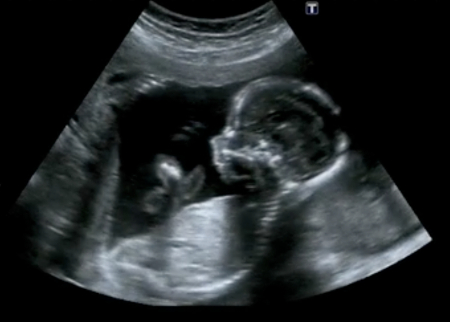

Katódcső segítségével a jelek látható "képpé" alakíthatók. Igaz, ez a kép nem azonos a fényképpel, mégis sok hasznos információt meríthet belőle a kicsit is gyakorlott szem. Ian Donald először nem a terhesség vizsgálatára használta az ultrahangot, hanem műtétre váró hasi daganatokat tekintett meg segítségével. 1957-ben alkalmazta először magzati elváltozások megfigyelésére, sőt 1963-ban magának a terhességnek a felismerésére is.

Egy skót tudós, Ian Donald figyelt fel rá 1950-ben, hogy némi hasonlóságot mutat a magzatvízben úszkáló magzat és a mélyre merült tengeralattjáró. Donald és munkatársai felhasználták a francia, angol és amerikai kutatók által kidolgozott technikát, s a módszer alkalmasnak látszott a magzat méhen belüli vizsgálatára.